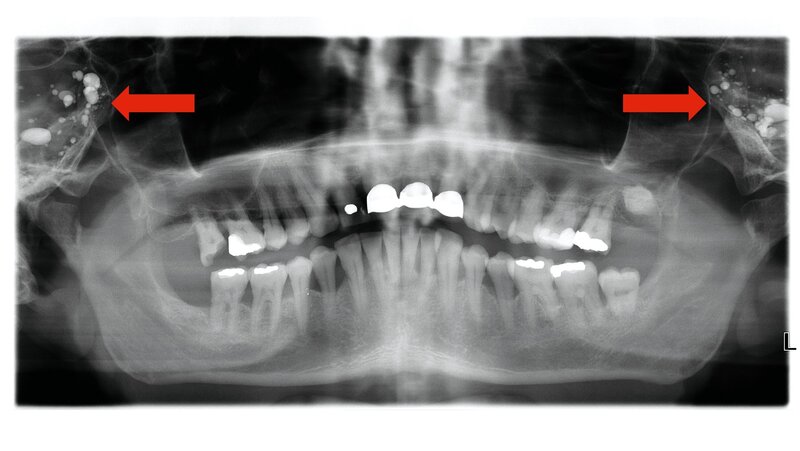

Bei der Befundung des OPGs fiel auf, dass sich beidseits über den Mastoidregionen multiple radiodense, oval- bis rundlich konfigurierte Strukturen projizierten. Diese imponierten in der Projektion sehr gleichmäßig und waren von ihrer Dichte her deutlich hyperdens gegenüber dem umgebenden Knochen. Aufgrund der ungewöhnlichen Lokalisation und Morphologie wurde zunächst differenzialdiagnostisch an verschiedene Verkalkungen oder Fremdkörper gedacht, jedoch konnte keine naheliegende Erklärung gefunden werden. Voraufnahmen waren nicht verfügbar.

Keine dieser Differenzialdiagnosen passte in unserem Fall – weder hinsichtlich der Lokalisation noch hinsichtlich der Morphologie oder der klinischen Konstellation. Daher erfolgte die weiterführende Diagnostik mittels Computertomografie (CT).